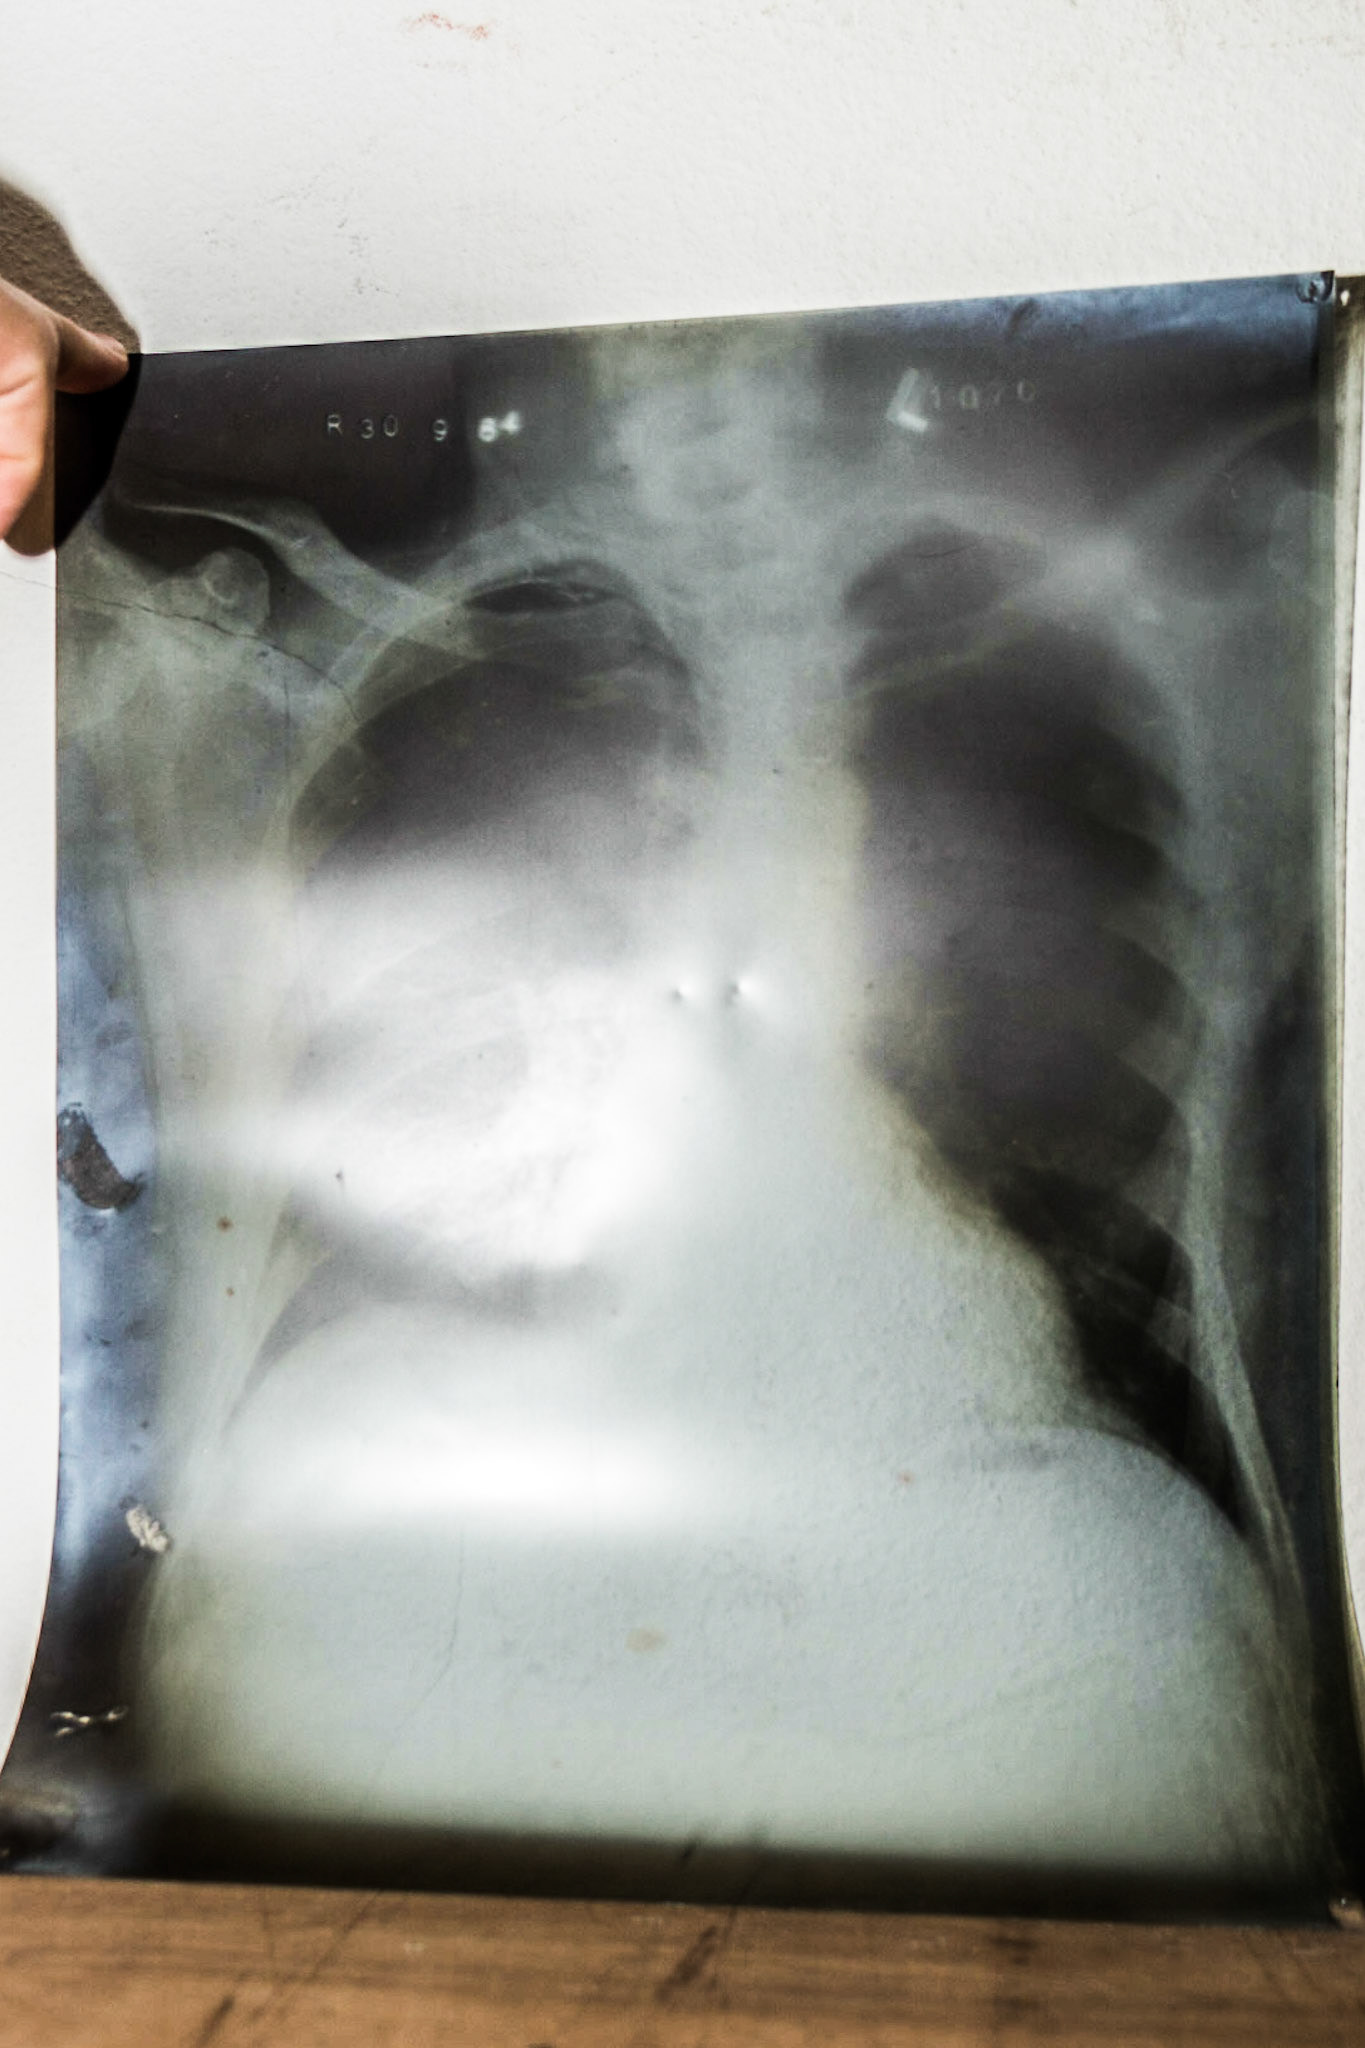

Cefn Coed hospital

Privately arranged visit to the recently closed mental hospital in Swansea. [28/7/18]